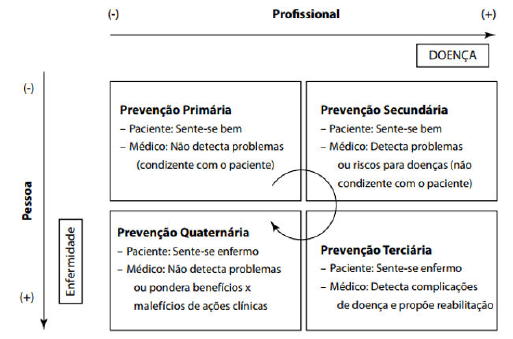

Observe os modelos de prevenção demonstrados a seguir:

No manejo da hipertensão arterial sistêmica de Dona Joaquina, que é diabética e sofreu um acidente vascular sistêmico há 6 meses, qual seria a melhor associação de medicamentos para prevenção de recorrência?